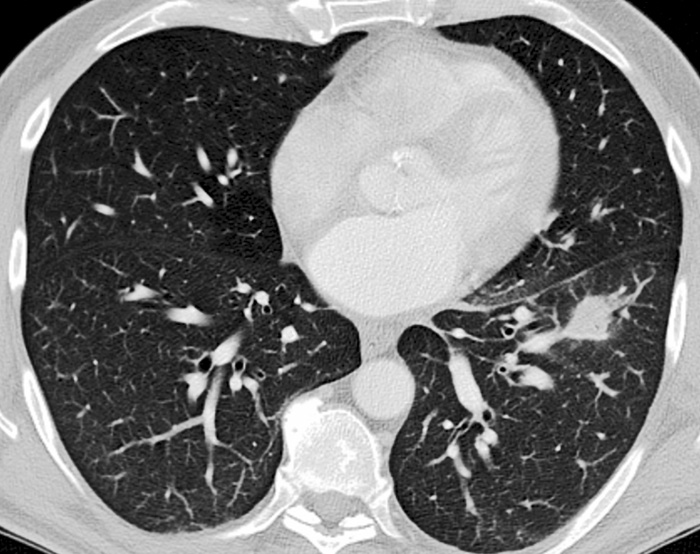

Figur 1B.  Tvärsnitt från datortomografi som visar förtätningen i vänster underlob respektive lymfkörtelför­storing i väns­ter lunghilus.

Figur 2A. 69-årig man med lungförändringar orsakade av tularemi (Fall 2). Tvärsnitt från datortomografi som visar en förtätning i vänster ovanlob, lingulasegmentet.

Fallet rör en 66-årig icke-rökande jordbruksarbetare som sökte för flanksmärta. Datortomografi (DT) visade en 2 cm stor förtätning i vänster underlob och körtelförstoringar i vänster lunghilus (Figur 1), varför patienten remitterades till lung- och allergikliniken och ingick i en s k snabbspårsutredning vid misstänkt lungcancer.

Fallet rör en tidigare frisk 69-årig man som aldrig hade rökt  och som insjuknade i övre luftvägsinfektion med besvärlig hosta. Husläkarens penicillin hade ingen effekt och därför beställdes lungröntgen och datortomografi, som utfördes en månad efter insjuknandet (Figur 2). Undersökningarna visade ett infiltrat basalt i vänster ovanlob, och patienten remitterades för misstänkt lungcancer. PET/DT med FDG visade spårämnesupptag i lunginfiltratet samt förstorade körtlar i lunghilus och para-aortalt med ökat upptag. Vid bronkoskopi fann man en kraftig inflammation, och PAD visade en nekrotiserande inflammatorisk process med granulom.